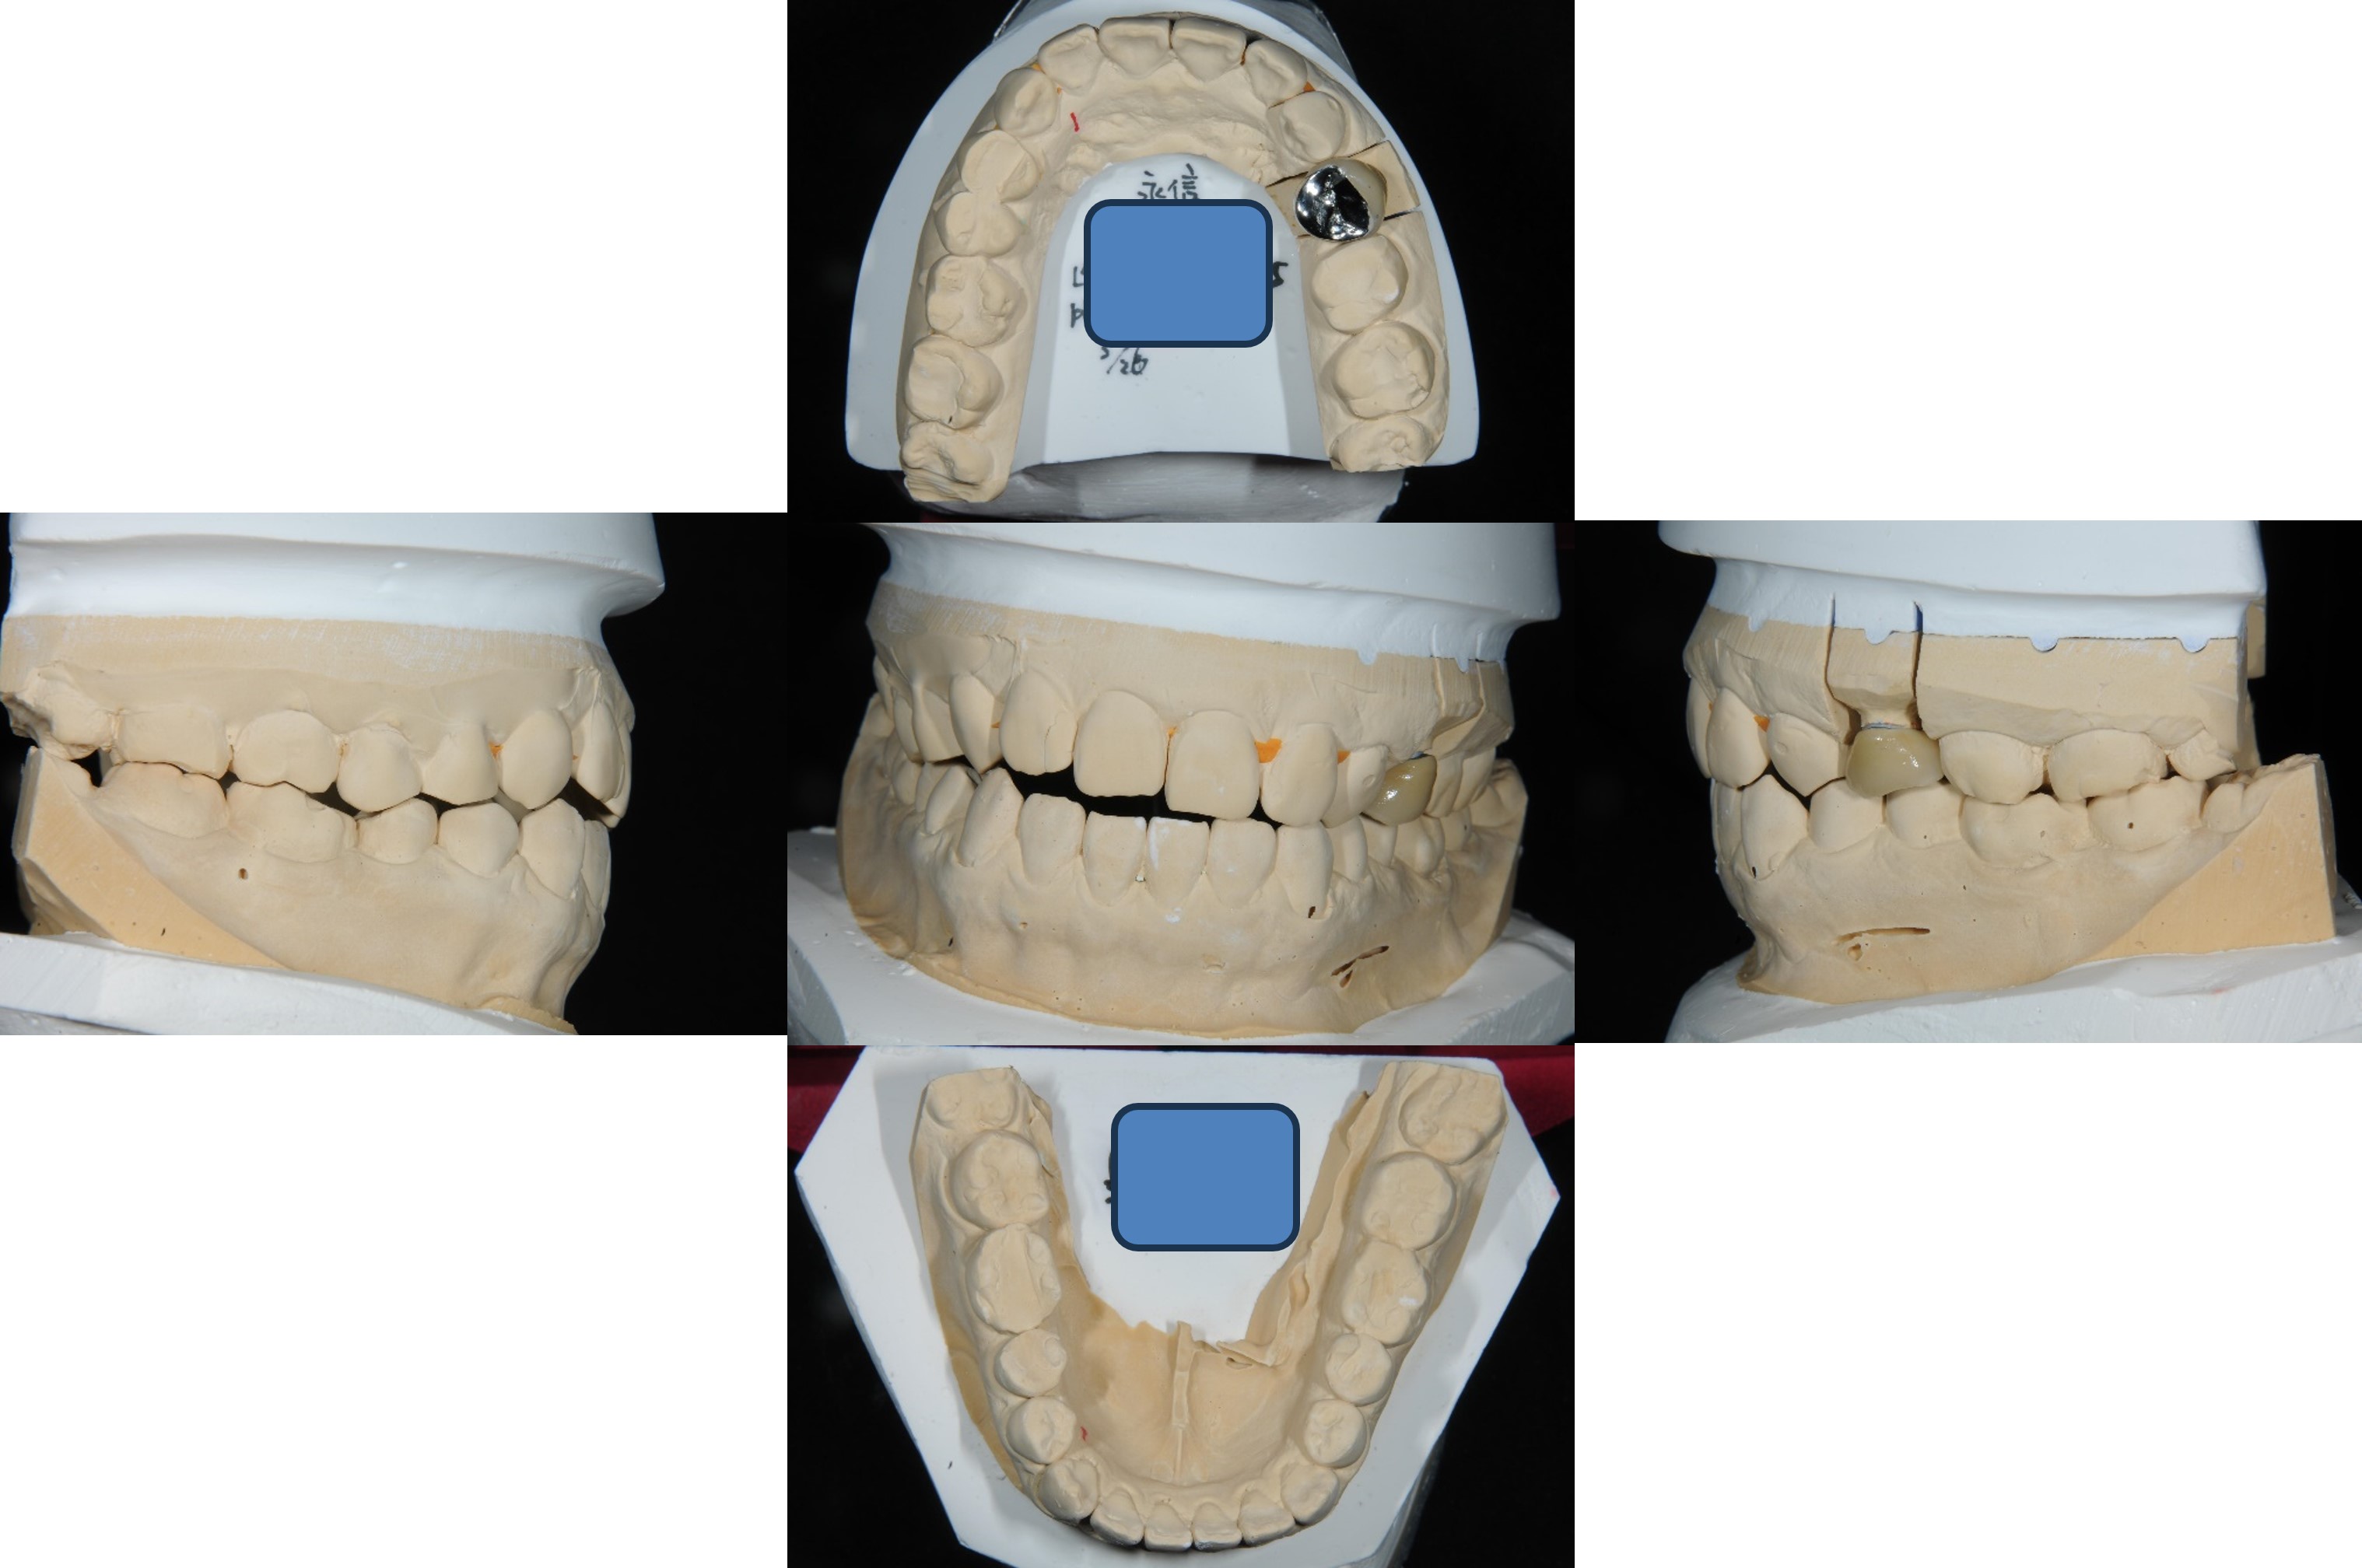

上面弓、上咬合器

技師於咬合器製作金屬燒付瓷牙

考量咬合面,製作金屬面之金屬燒付瓷牙